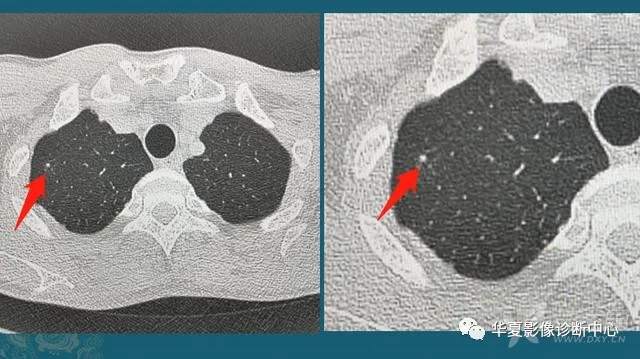

下图是两位女士,左图是当年在萤石矿上打工,当时条件简陋防护不到位,长期吸入粉尘,在肺里形成很多小结节:

右图是一位采棉女工,长期吸入植物性粉尘,在肺里形成很多微结节和索条状影。

类似的尘肺病包括13种,包括矽肺、煤工尘肺、焊工尘肺等。既往尘肺分为致纤维性尘肺(危害大)和非致纤维性尘肺,矽肺、石棉肺、滑石尘肺为致纤维性尘肺;而吸入某些金属粉尘(如铁、钼),在肺组织内呈现一般的异物反应,脱离粉尘后可以逐渐减弱,对人体危害较小。